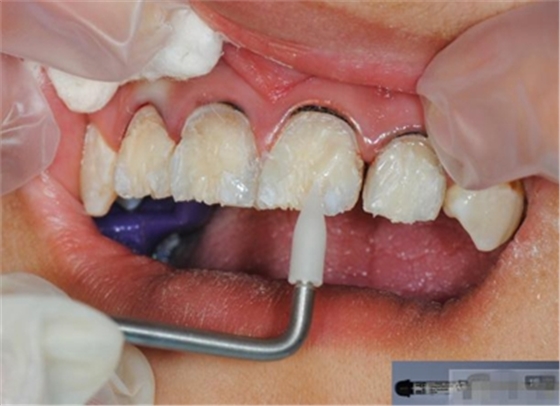

【纖維樁制作】

修整纖維樁長(zhǎng)度

取出纖維樁,按所需長(zhǎng)度裁截纖維樁 在有水條件下 用切割砂片或車針截取纖維樁,切勿使用鉗子,剪刀或鑷子以免破壞樁的結(jié)構(gòu)

涂布硅烷偶聯(lián)劑

涂布粘接劑

將樹(shù)脂粘接劑均勻涂抹在根管、牙體的粘接面以及纖維樁表面,涂抹兩遍

粘接

將調(diào)好的樹(shù)脂水門汀用口內(nèi)注射頭送入根管

將纖維樁表面涂滿調(diào)好的樹(shù)脂水門汀,安放在根管內(nèi)就位,保持壓力10秒